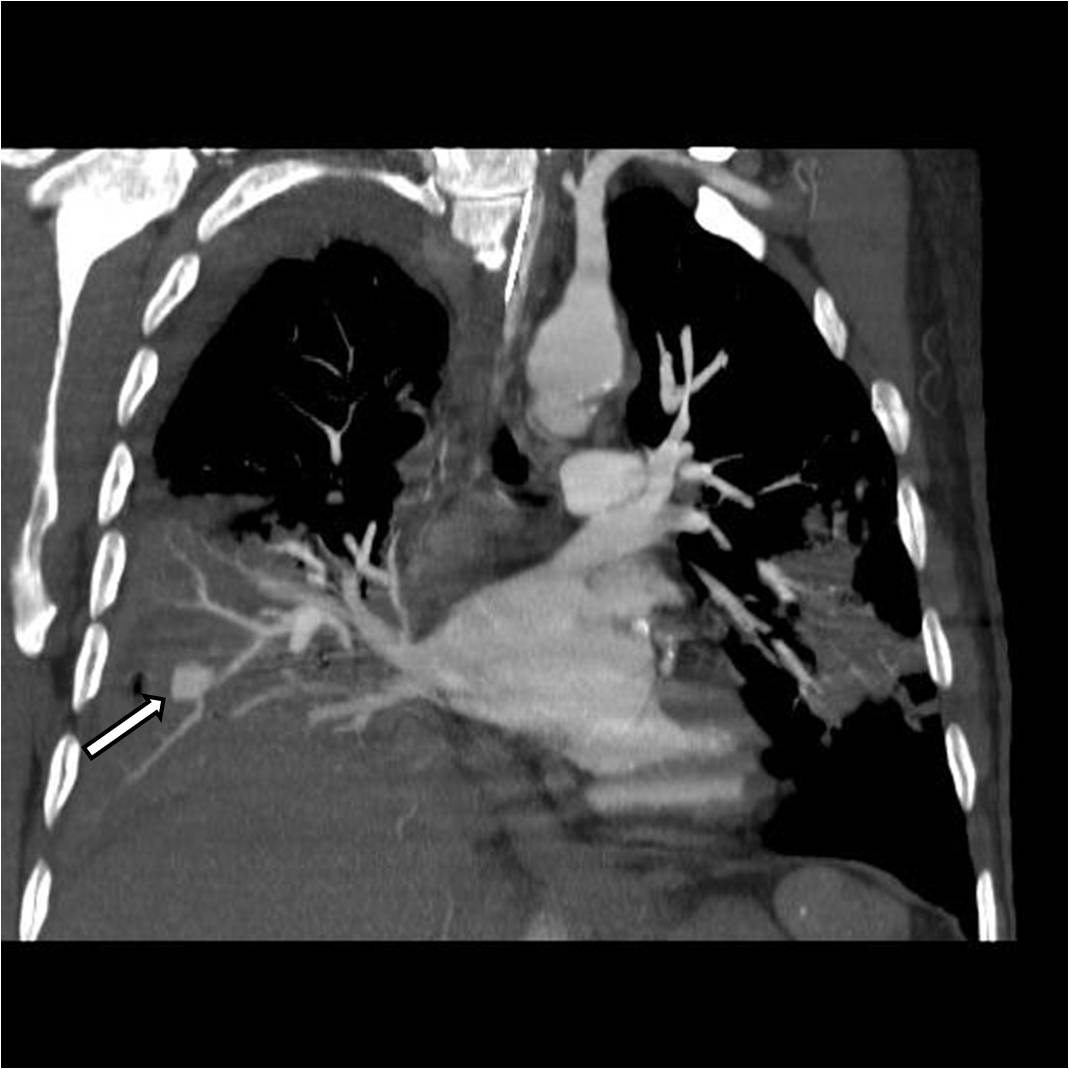

Figures